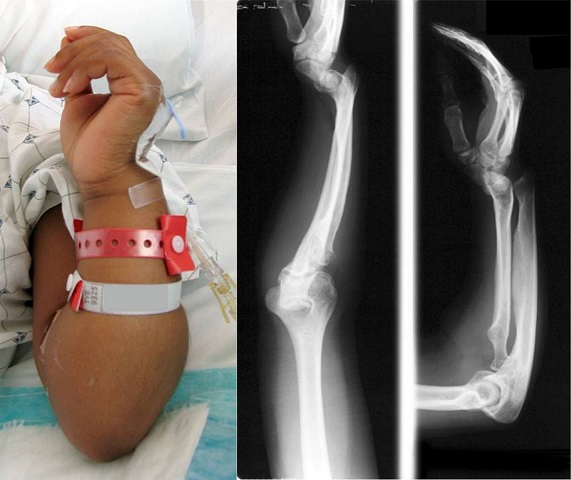

ر) شکستگی صفحه رشد انتهای پایینی استخوان رادیوس در مچ دست

شایعترین نوع شکستگی در قسمت پایینی استخوان رادیوس یا زند زبرین شکستگی کالیس است. شکستگی کالیس نوعی شکستگی دیستال استخوان رادیوس ( قسمت انتهایی استخوان رادیوس یا زند زبرین که نزدیک مچ دست قرار دارد) است که در آن قطعه شکسته شده که به مفصل مچ دست متصل است به سمت دورسال یا پشتی جابجا میشود ( منظور از سطح دورسال یا پشتی یعنی به طرف پشت دست یا پشت مچ دست که مخالف طرف کف دستی است).

گاهی اوقات ضرباتی که به انتهای پایینی استخوان رادیوس وارد میشود موجب آسیب به این ناحیه ولی با شکلی متفاوت از شکستگی کالیس میشود . یکی از این اشکال متفاوت، شکستگی صفحه رشد انتهای پایینی استخوان زند زبرین است .صفحه رشد صفحه ای از جنس غضروف است که در انتها های استخوان های بلند قرار داشته و با فعالیت خود موجب رشد طولی استخوان میشود. در انتهای پایینی استخوان رادیوس یک صفحه رشد قرار دارد. صفحه رشد در تصویر رادیوگرافی معمولا به صورت یک خط سیاه رنگ دیده میشود .

مکانیسم شکستگی صفحه رشد انتهای پایین استخوان رادیوس شبیه شکستگی کالیس است. تفاوت در این است که این شکستگی در کسانی ایجاد میشود که هنوز صفحه رشد انتهای پایینی استخوان آنها باز و فعال است. پس این شکستگی در بچه ها و نوجوانان ایجاد میشود. این شکستگی ها معمولا از نوع سالتر هاریس دو هستند .

شکستگی صفحه رشد انتهای پایینی استخوان زند اعلی را نباید با شکستگی باکل یا توروس اشتباه کرد. شکستگی باکل (توروس) نوعی شکستگی ترکه تری در بالاتر از صفحه رشد است .

درمان شکستگی صفحه رشد انتهای پایینی استخوان رادیوس در غالب اوقات بصورت جااندازی بسته و گچ گیری است. در مواردی که شکستگی بصورت بسته جا نمی افتد اقدام به جا اندازی باز و فیکس کردن قطعات با پین میشود .